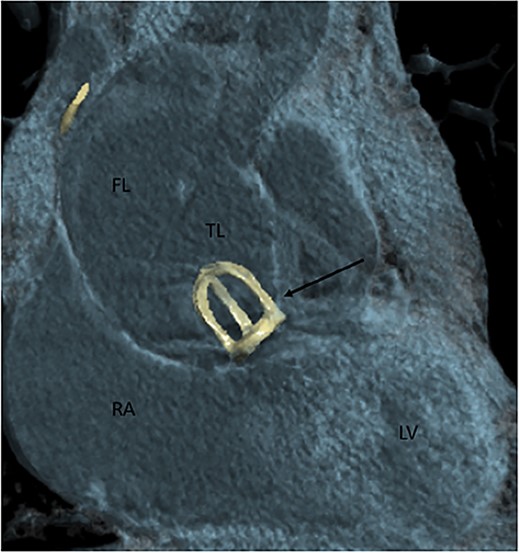

A 77-year-old male patient presented to the emergency department with chest pain which started a couple of hours before. His medical history is significant of surgical AVR with a mechanical caged-ball prosthesis 40 years prior due to aortic stenosis and atrial fibrillation. Unfortunately, he presented no medical records regarding the previous AVR. Therefore we did not know what was the pathology of the aortic valve at the time. He was anticoagulated with warfarin and at the time of presentation was in a therapeutic range, with an international normalized ration value of 3.01. During the observation in the emergency department, the patient sustained a cardiac arrest with pulseless electrical activity verified on the electrocardiogram. He was successfully resuscitated and promptly transferred to the cardiovascular intensive care unit (CICU). At the time of the CICU admission, the patient had elevated blood lactate levels and was acidotic, and vasopressor support with norepinephrine was initiated. Urgent coronary angiography was performed which showed the absence of coronary artery disease, normal function of the caged-ball prosthesis, and a dilated ascending aorta. Computed tomography (CT) aortography due to the aortic aneurysm was then performed, and the diagnosis of the Stanford A dissection was made. The ascending aorta was up to 60 mm wide, and communication between the false and true lumen was described in a proximal ascending part of the vessel (Fig. 1). Hemopericardium up to 24 mm was also described.

Contrast-enhanced CT aortography coronal plane in volume rendering technique reconstruction. Stanford A dissection distal to artificial caged-ball (thin arrow) mechanical valve. FL, false lumen; TL, true lumen; RA, right atrium; LV, left ventricle.